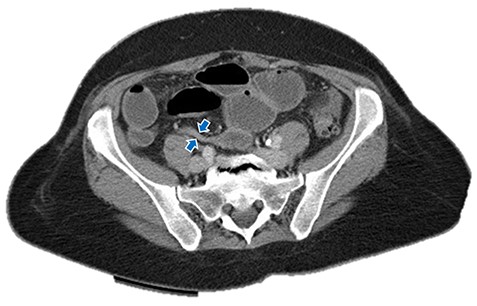

Immediate postoperative course was uneventful until postoperative day (POD)-5 when she experienced multiple watery stools, diffuse abdominal pain, fever (102.6F) and leukocytosis (23000/UL). Clostridium difficile infection was ruled out with a negative stool toxin assay. Her abdominal exam remained nonspecific until POD-6 when she had bilious emesis. A computed tomography (CT) scan revealed perforated diverticulitis with pelvic abscess and multiple colonic diverticulitis with an associated small bowel obstruction (SBO) (Images 1–4). No prior history of diverticulitis was reported.

Small bowel obstruction showing air-fluid levels with transition point in the distal ileum. Blue arrows: small bowel obstruction with transition point in distal ileum.